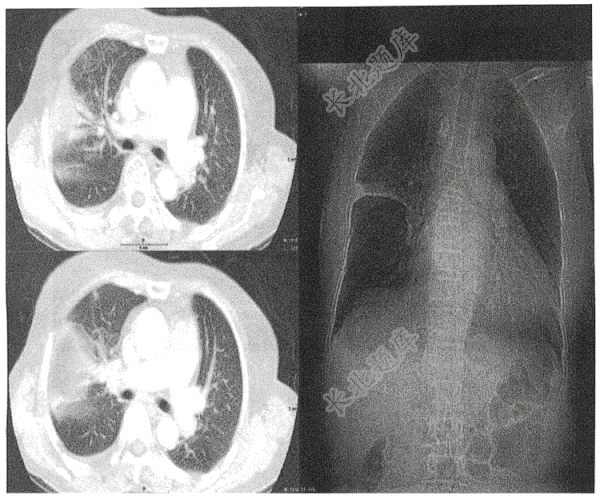

- 单项选择题男性,61岁发热( )

A、右肺上叶周围型肺癌伴空洞

B、右肺上叶肺炎

C、右肺上叶脓肿伴空洞

D、右肺上叶浸润性结核

E、右肺上叶包裹性积液